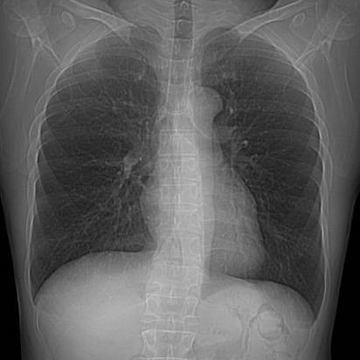

肺をスライスした画像を撮影し、病気を見つける検査です。

胸部エックス線よりも早期のがんの検出に優れています。

また肺だけでなく、呼吸器疾患や、血管疾患も検知することができます。